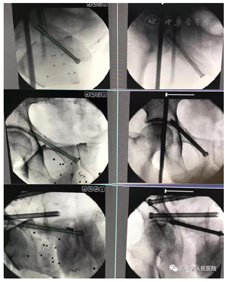

前方救援队员到达后,发现伤员病情仍不稳定,血红蛋白持续性下降,启动5G紧急医学救援系统,与后方专家组共同再次评估伤员。通过实时回传的超声图像,专家组发现伤员腹腔积液,疑似内脏器官破裂出血(图2)。建议先行选择性数字减影血管造影(digital substraction angiography,DSA)及血管栓塞控制出血后再行剖腹探查手术。但是现场不具备DSA能力,在当地有限的医疗资源下行剖腹探查手术风险极高。是否转运到后方医院进一步治疗成为一大难题。最终,前方队员与后方专家组讨论后决定,只有航空转运才能耗时最短,最大程度的保障伤员生命安全。抢救8 h后,伤员由AW119专业医疗直升机经过90 min的空中转运到达四川省人民医院急救中心。增强CT发现肝脏破裂(图3A),立即进行骨盆及肝脏DSA及选择性血管栓塞止血治疗(图3B),使得出血得到有效控制后即刻行损伤控制手术,术中证实肝脏破裂,行肝修补术(图3C)。手术后回到急诊监护室进一步复苏治疗,患者病情逐渐稳定。第2天,经过多学科专家团队评估后,认为伤员不稳定性骨盆骨折,失血量大,宜尽早进行机器人引导的微创骨盆骨折内固定术(图4)。